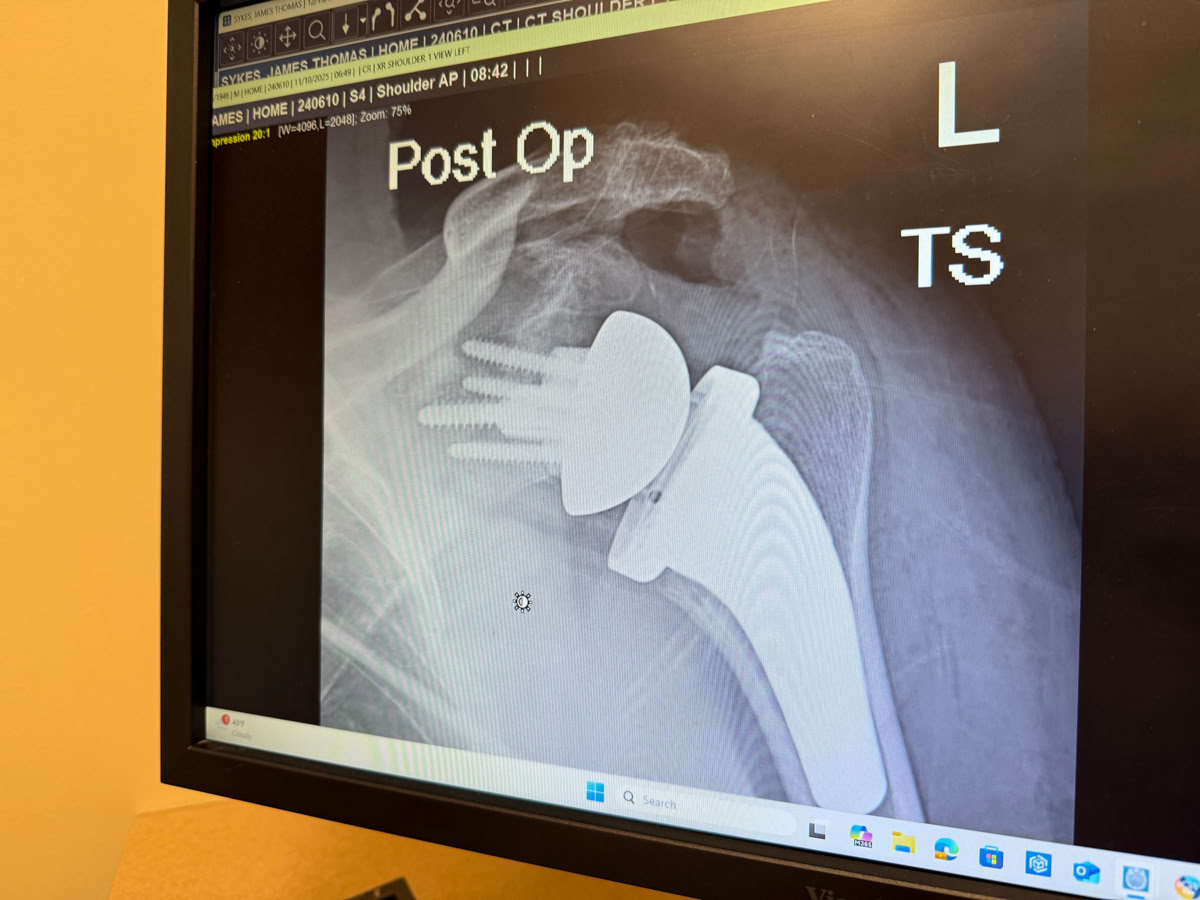

January found us heading to northern Minnesota to catch up with winter birding, something we’d not done for years.  February was Tom’s reverse shoulder replacement surgery (followed by months of physical therapy). April it was Carol’s turn - a new hip. And more PT. As we were once more living in Wisconsin, there was not need for an annual return visit. Instead we availed ourselves of farmers markets, supper clubs and seeing more of family. However, August required a trip west to Wyoming to attend granddaughter Cali’s outdoor wedding to her fiancé Daniel. September held two reunions. One for Carol’s family and the second Tom’s 60th high reunion. By the time November rolled around it was time for our bird tour to Northwest Argentina. Alas, owing to some unseen physical issues, Carol’s mobility prevented her from going on the tour. Shortly after Tom’s return from Argentina, it was time for his second reverse shoulder replacement surgery. The remainder of the year will be overshadowed by more physical therapy as we work our way through the holidays.